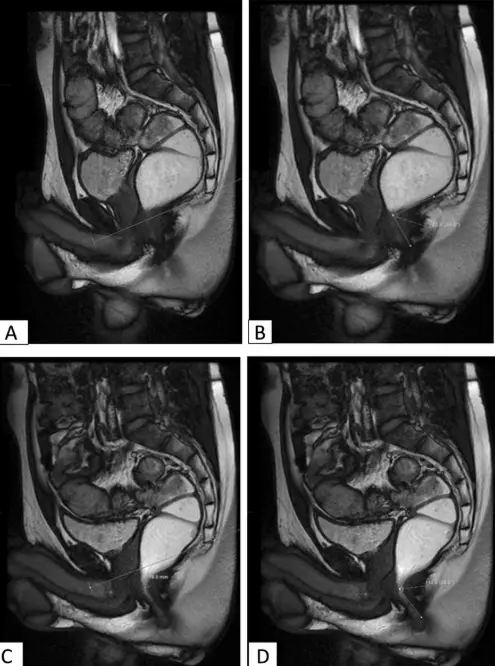

Figure 14: Botched hemorrhoidal surgery in an unlicensed outlet offering guaranteed outcome through non-operative means. The patient presented with chronic rectal discharge, bleeding, and severe pain a week following the outpatient treatment received from the clinic. A colonoscopy revealed large ulceration denoting recent procedures performed, the location of these ulcers were far away from the area where the haemorrhoids were supposed to be. Further to this, a fistula – an abnormal connection between the rectal walls and the perianal region (where fats are located) has formed leading to pus collection and infection. An MRI confirmed all these findings and the fistulous connection resulting from a through-and-through tear (perforation) from the lining of the rectum to the peri-rectal fat.